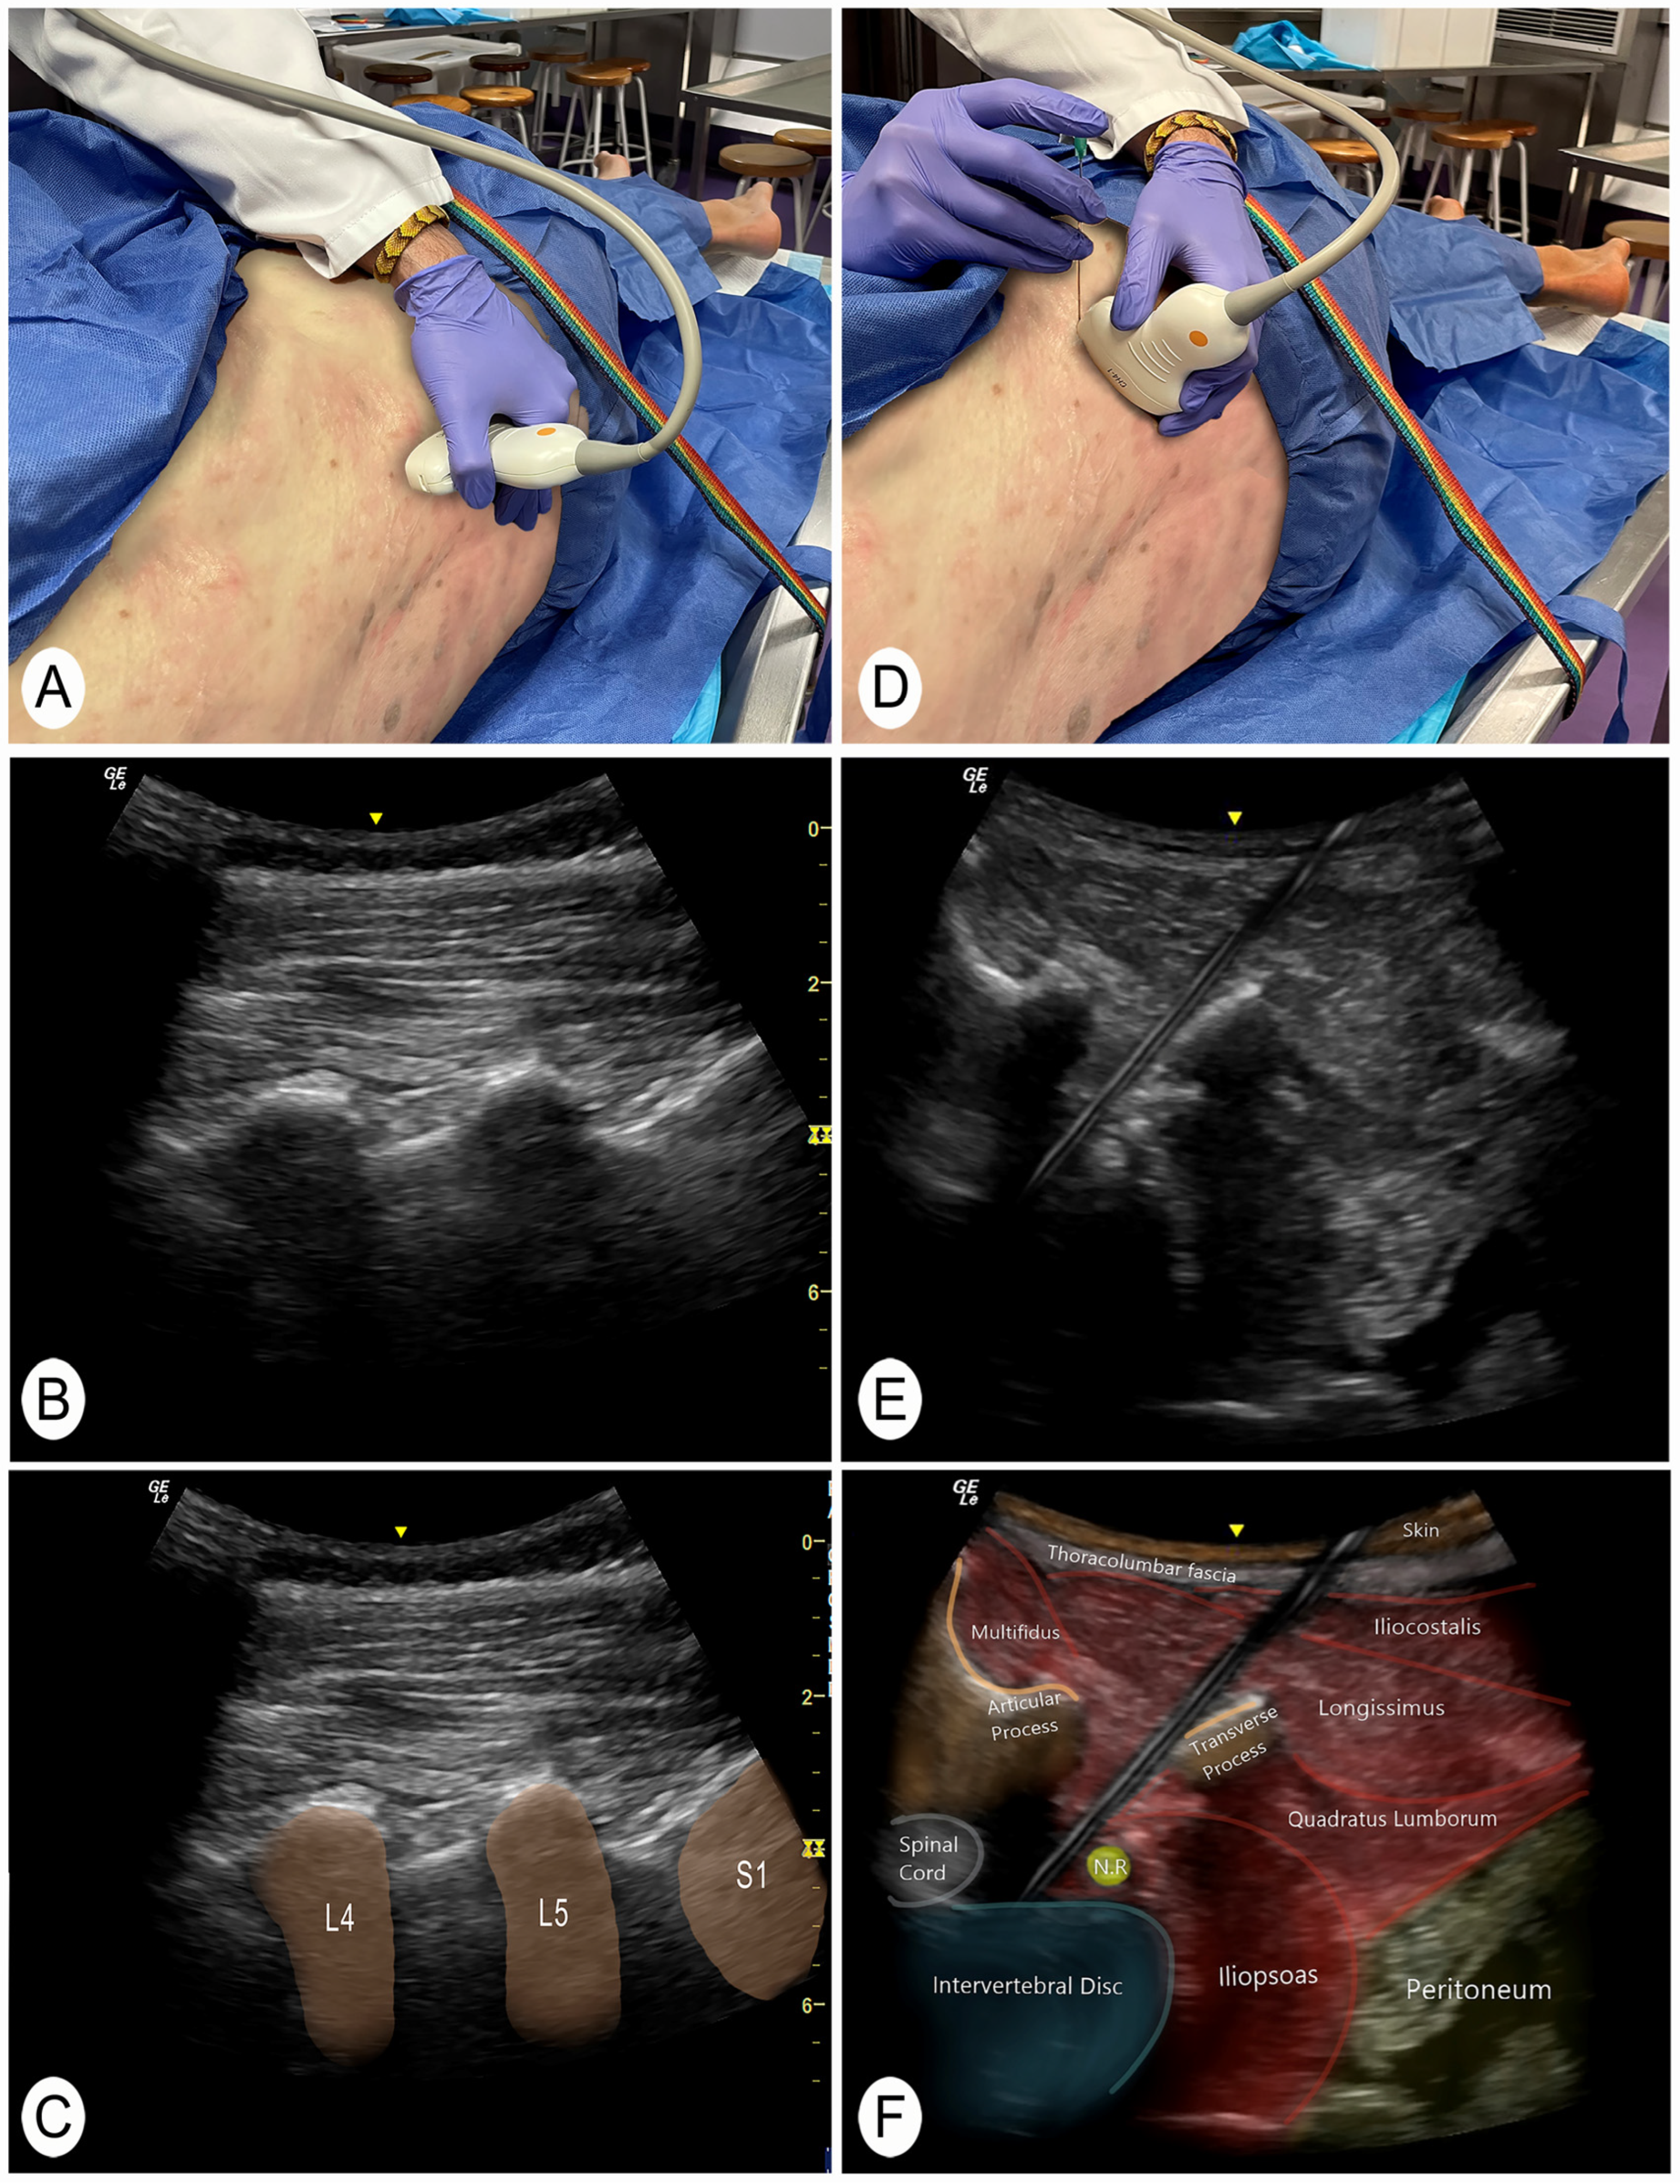

2.3. Ultrasound-Guided Needling Approach

| L1 (n = 12) | L2 (n = 12) | L3 (n = 12) | L4 (n = 12) | L5 (n = 12) | Global (n = 60) | |

|---|---|---|---|---|---|---|

| Length of the needle introduced (mm) | 75 ± 9 | 73 ± 15 | 81 ± 12 | 86 ± 16 | 81 ± 18 | 79 ± 15 |

| Angulation of the needle (°) | 134.9 ± 23.8 | 137.7 ± 14.3 | 131.0 ± 20.4 | 124.5 ± 18.8 | 116.7 ± 15.3 | 129.0 ± 20.2 |

| Reach the posterolateral part of the discs | 91.7% | 100% | 100% | 91.7% | 83.3% | 93.3% |

| Distance from the vertebral spine to the needle (mm) | 80 ± 15 | 78 ± 15 | 83 ± 22 | 77 ± 23 | 67 ± 20 | 77 ± 19 |

| Distance of the needle to the main nerve roots (mm) | 2.1 ± 0.6 | 2.2 ± 0.8 | 2.3 ± 2.0 | 1.8 ± 1.0 | 1.6 ± 0.7 | 2.0 ± 1.2 |

| Unwanted structures crossed | - | - | - | - | 1 nerve root | 1 nerve root |